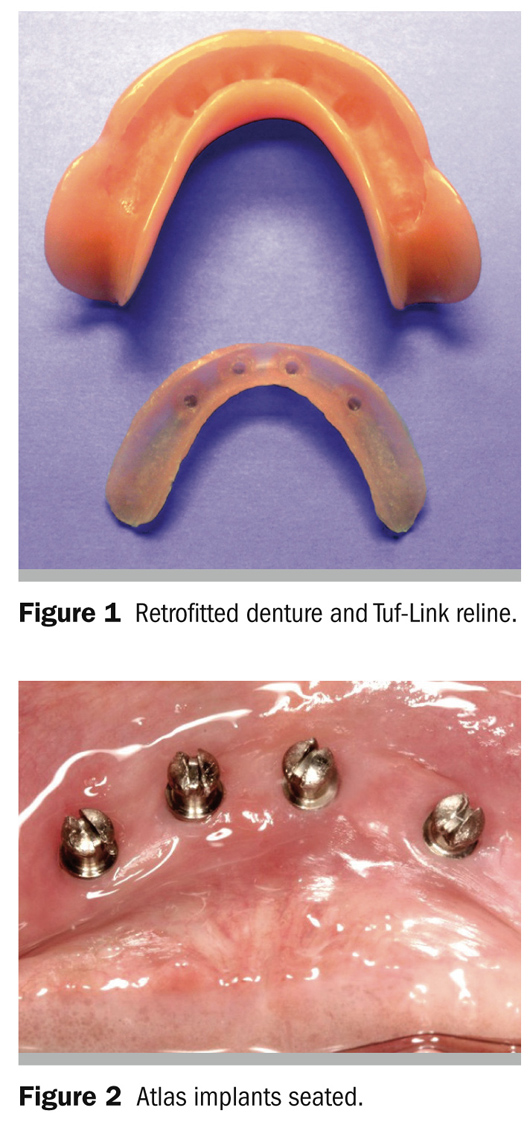

The Dentatus Atlas proprietary design overcomes the known rigid denture limitations with Tuf-Link® silicone reline material (Figure 1), accommodating the broad range of the diverse conditions of edentulism.

Osteotomies are then refined with reamers made for the wider 2.2-mm or 2.4-mm Atlas Implants. In hard D1 or D2 bone, the osteotomies are made 1 mm to 1.5 mm deeper to prevent bottoming out resistance that could prevent the implant platform to seat in the surrounding soft tissue. The sterilized, surface-textured implants are packaged with a driver cap used to initially stabilize the implant without direct contact or possible contamination; this is followed up by using a latch driver for a low-speed R/A handpiece. The installation is completed with the tactile manual winged driver. The tapered platform of the implant should seat flush with the surrounding soft tissue (Figure 2).